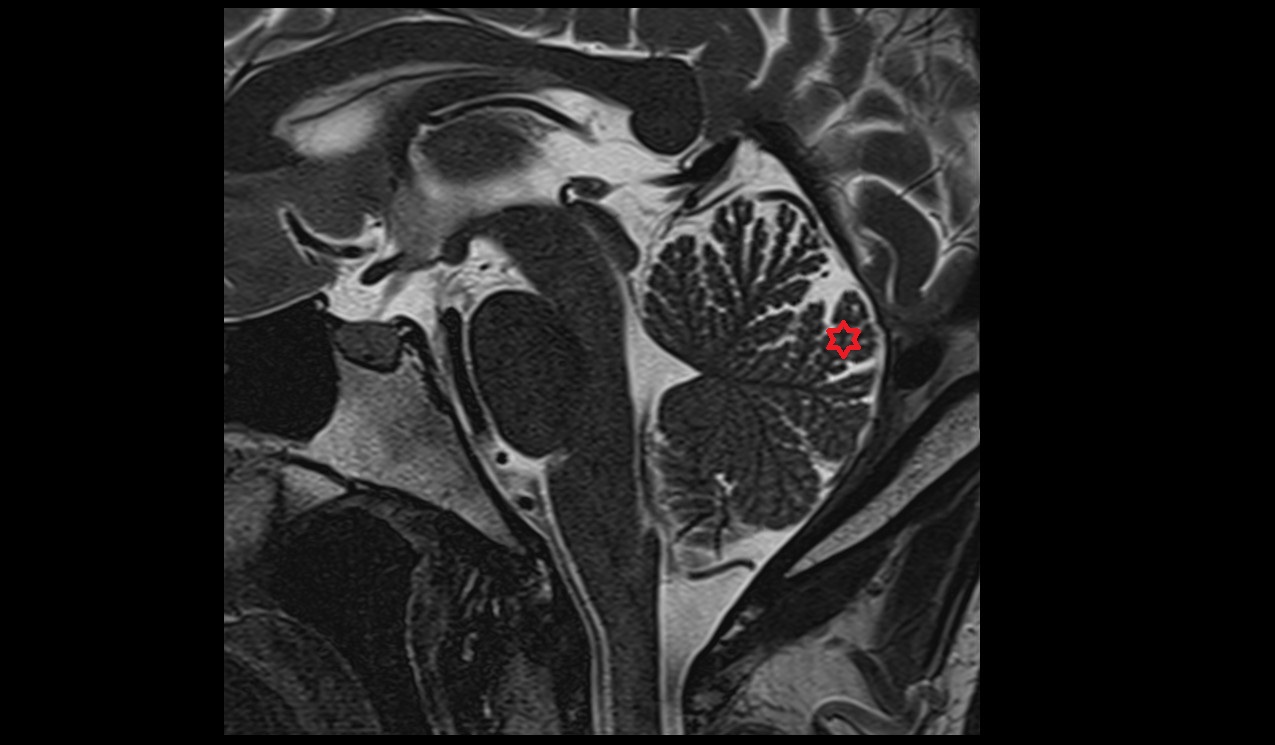

- Tonsil of cerebellum

- Cisterna magna

- Median aperture of fourth ventricle (foramen of Magendie)

- Lingula of cerebellum (I)

- Nodule of vermis (X)

- Cerebellar tonsil (H IX)